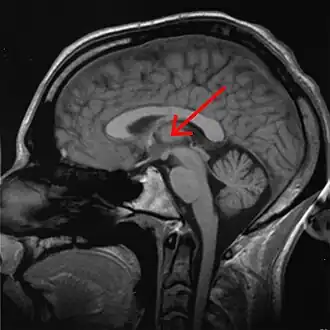

The thalamus (pl.: thalami; from Greek θάλαμος, "chamber") is a large mass of gray matter on the lateral wall of the third ventricle forming the dorsal part of the diencephalon (a division of the forebrain). Nerve fibers project out of the thalamus to the cerebral cortex in all directions, known as the thalamocortical radiations, allowing hub-like exchanges of information. It has several functions, such as the relaying of sensory and motor signals to the cerebral cortex[1][2] and the regulation of consciousness, sleep, and alertness.[3][4]

Anatomically, the thalami are paramedian symmetrical structures (left and right), within the vertebrate brain, situated between the cerebral cortex and the midbrain. It forms during embryonic development as the main product of the diencephalon, as first recognized by the Swiss embryologist and anatomist Wilhelm His Sr. in 1893.[5]

The thalami are paired structures of gray matter about four centimetres long and ovoid in appearance,[6] located in the forebrain which is superior to the midbrain, near the center of the brain with nerve fibers projecting out to the cerebral cortex in all directions. In fact, almost all thalamic neurons (with the notable exception of the thalamic reticular nucleus[7]) project to the cerebral cortex, and every region of the cortex so far studied has been found to innervate the thalamus.[8]